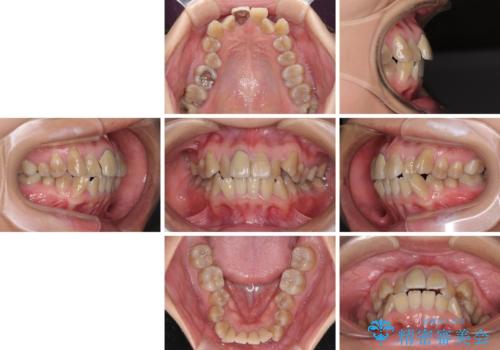

八重歯とクロスバイト 目立たないワイヤー装置での抜歯矯正

- 八重歯や前歯のデコボコを気にして来院された患者様です。

歯列が前方に傾斜しており、デコボコが強かったため、上下左右第一小臼歯4歯を抜去し、ワイヤー装置による矯正治療を行うこととしました。

上下の正中がずれていましたが、抜歯矯正であったので、極力正中位置を合わせるように治療を進めて行きました。

顎間ゴムの使用などにより、正中位置を改善することができました。